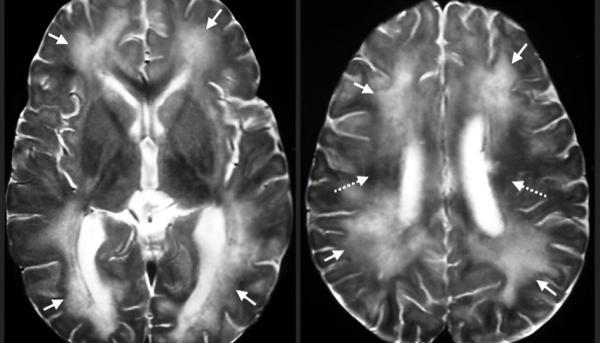

تعد هذه العدوى شديدة الخطورة عند انتقالها للبشر، حيث قد تؤدي إلى شلل دماغي، وفقدان البصر، وأحياناً الوفاة. وتظهر الأعراض تدريجياً خلال أسبوع من الإصابة، وتشمل الغثيان، تضخّم الكبد، وفقدان السيطرة على العضلات، وصولاً إلى الدخول في غيبوبة.